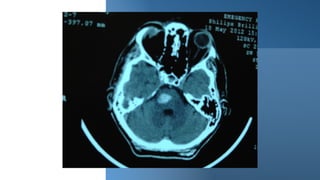

Quadriparesis: brain/high cervical cord MRI, with or without contrast. Brain CT

reveal a diagnosis, e.g., pontine hemorrhage.

Other pareses? Quadriparesis: brain/highcervical cord MRI, with or without contrast. Brain CT scan can also be used in the acute setting; depending on the etiology, it may reveal a diagnosis, e.g., pontine hemorrhage. Other pareses: Beyond undergraduates!